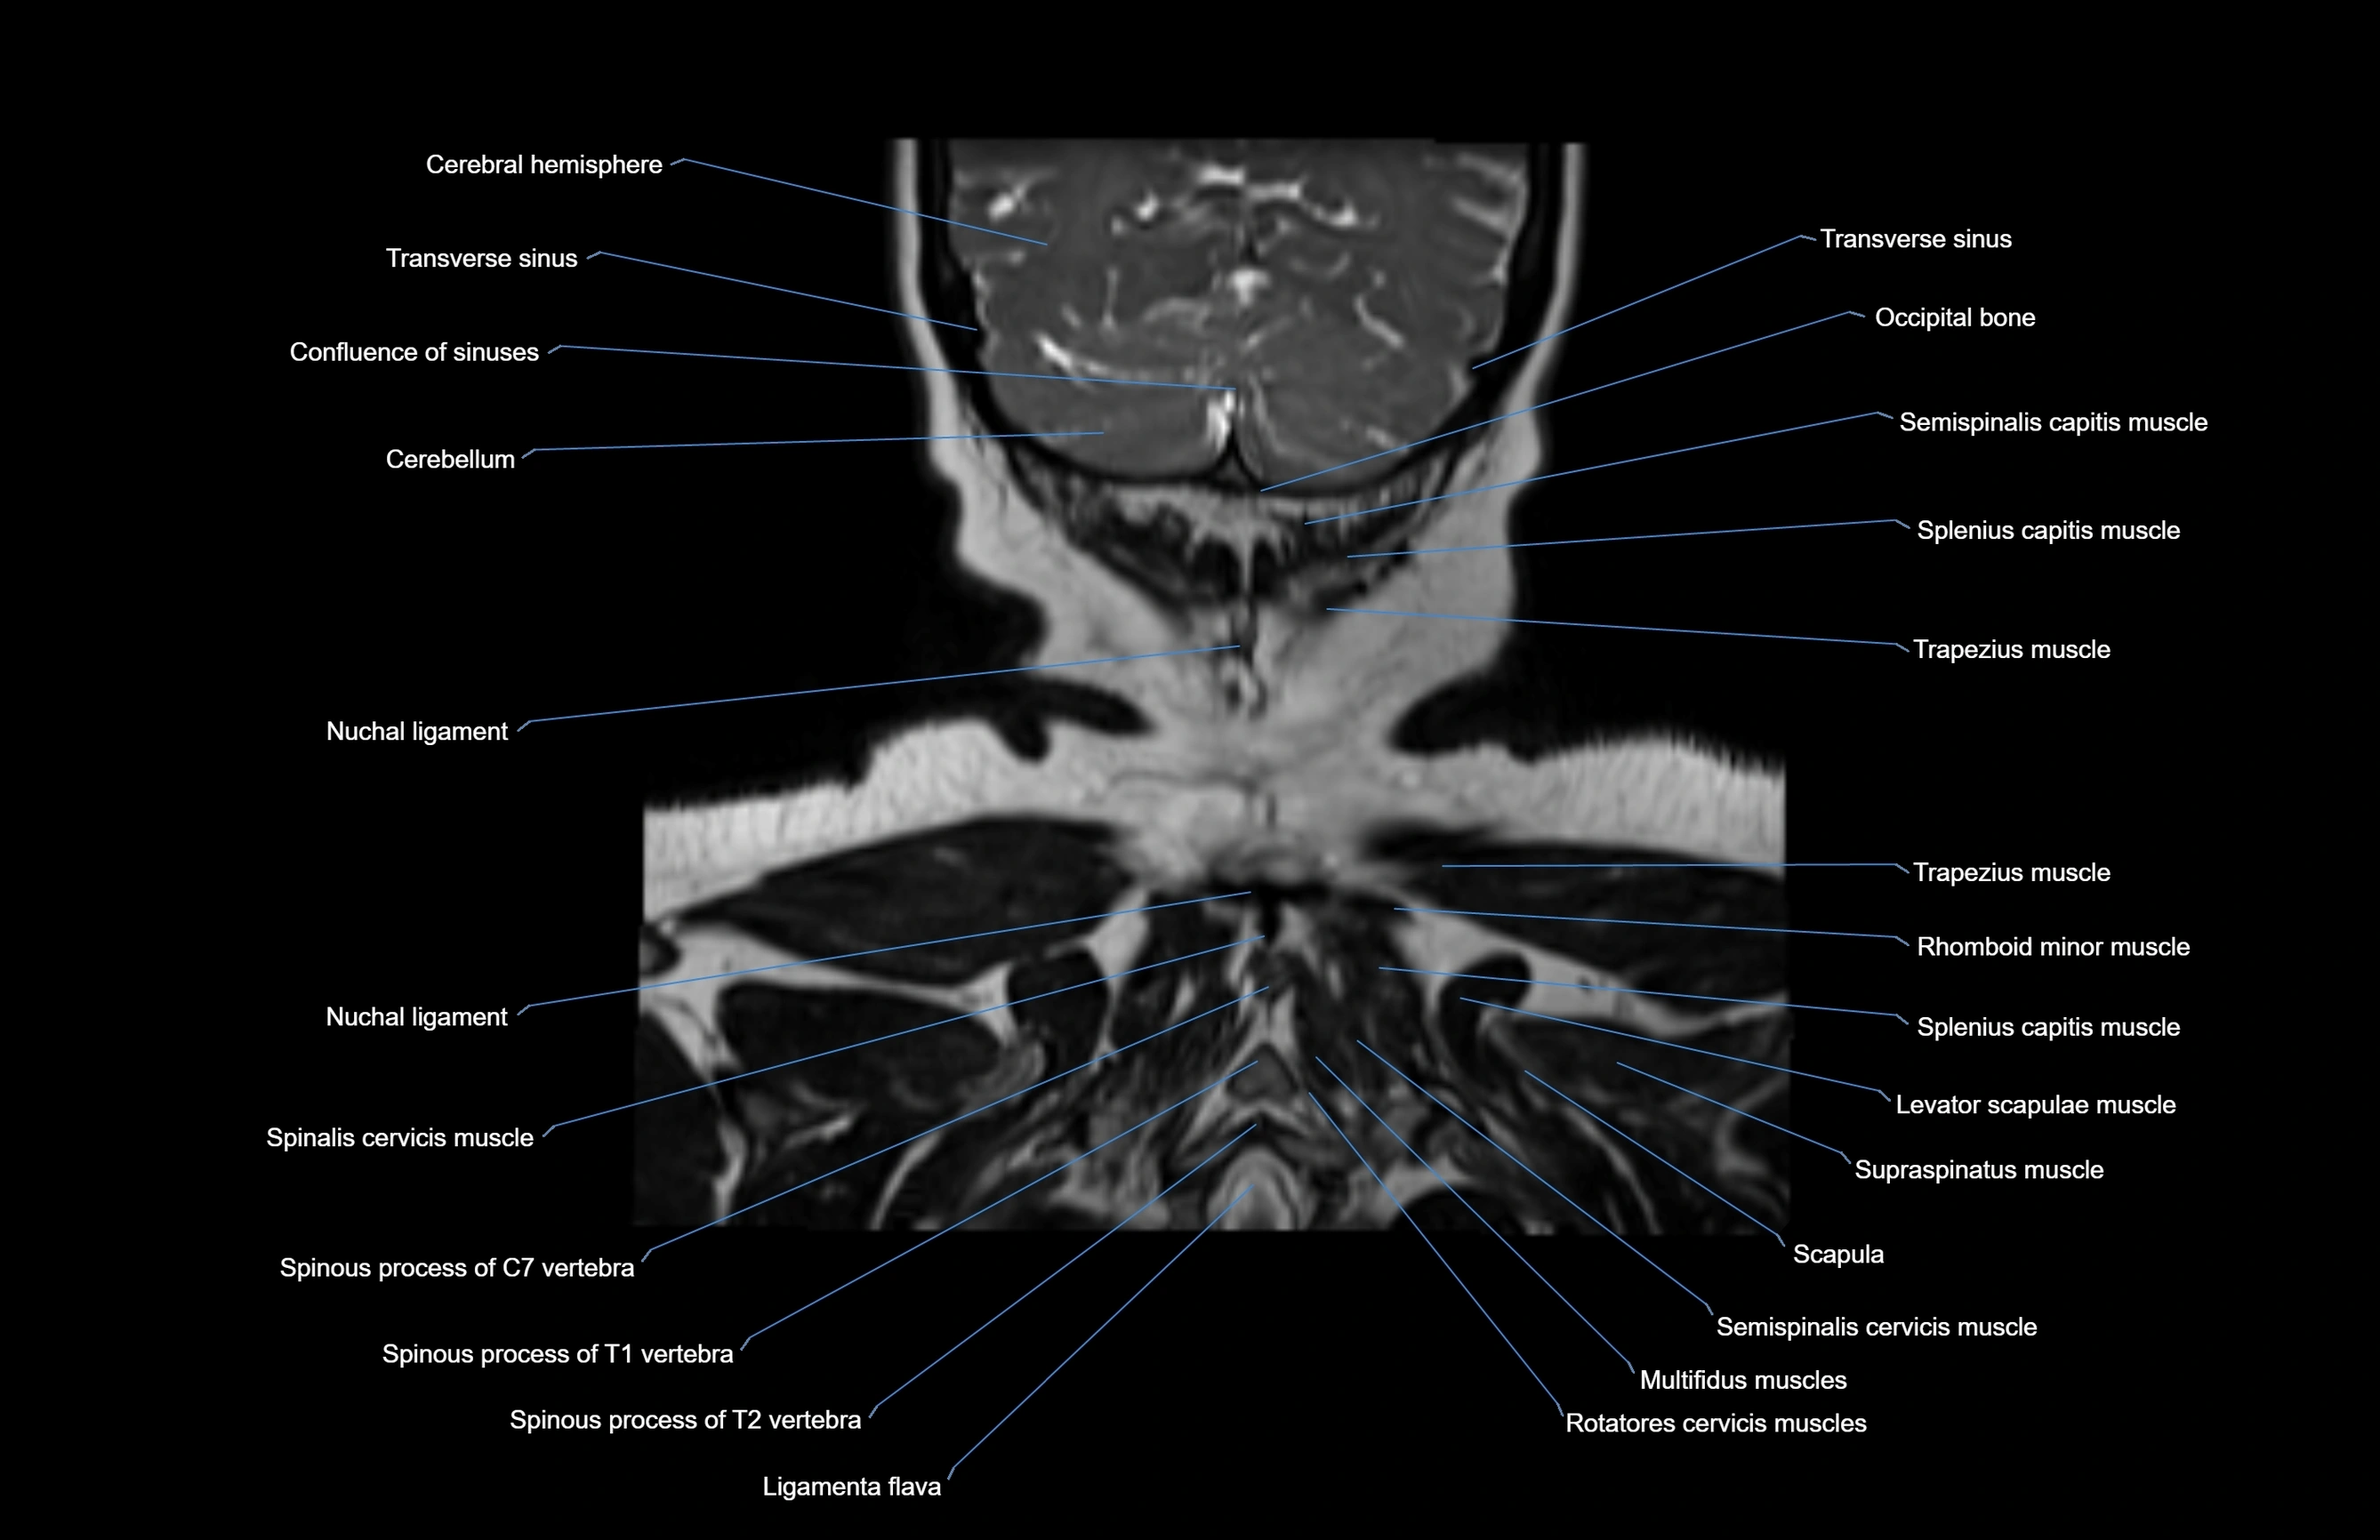

- Multifidus muscles

- Nuchal ligament

- Occipital bone

- Rhomboid minor muscle

- Rotatores cervicis muscles

- Scapula

- Semispinalis capitis muscle

- Semispinalis cervicis muscle

- Spinalis cervicis muscle

- Splenius capitis muscle

- Splenius cervicis muscle

- Supraspinatus muscle

- Trapezius muscle